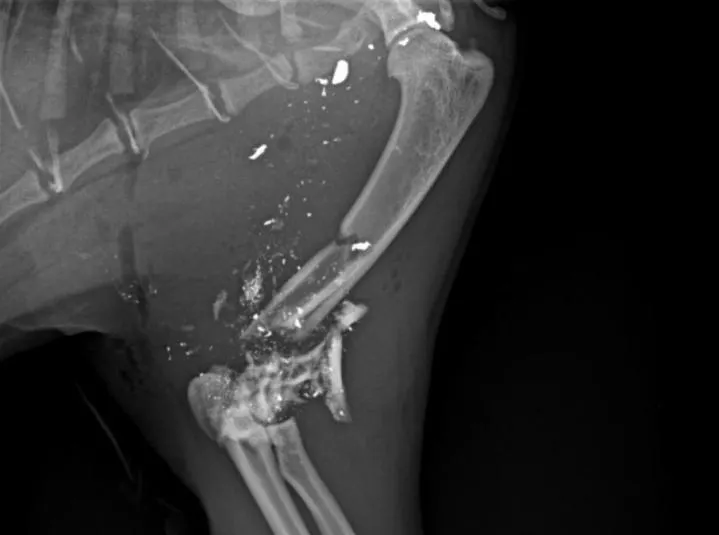

Le vétérinaire fait passer une radio à Jack. « Quand il est revenu, il nous a dit que notre chat s’était pris une balle. Qu’on lui avait tiré dessus. L’intérieur de la patte est complètement explosé. Les taches blanches que l’on voit sur la radio, ce sont des fragments de balle. On va essayer d’en récupérer pour les apporter à la police. »

Sur la radio prise par le vétérinaire, on voit des taches blanches, qui sont en fait des extraits de balle. Clinique Anovet